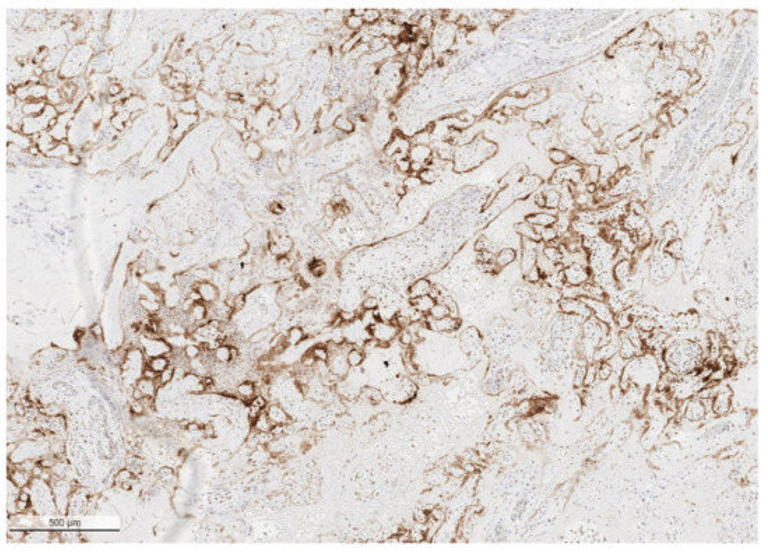

Stillbirth is a recently recognized complication of COVID-19 in pregnant women. Other congenitally transmitted infections from viruses, bacteria and parasites can cause stillbirth by infecting fetal organs following transplacental transmission of the agent from the maternal bloodstream. However, recent research on pregnant women with COVID-19 having stillbirths indicates that there is another mechanism of stillbirth that can occur in placentas infected with SARS-CoV-2. In these cases, viral infection of the placenta results in SARS-CoV-2 placentitis, a combination of concurrent destructive findings that include increased fibrin deposition which typically reaches the level of massive perivillous fibrin deposition, chronic histiocytic intervillositis and trophoblast necrosis. These three pathological lesions, in some cases together with placental hemorrhage, thrombohematomas and villitis, result in severe and diffuse placental parenchymal destruction. This pathology can involve greater than one-half of the placental volume, averaging 77% in the largest study of 68 cases, effectively rendering the placenta incapable of performing its function of oxygenating the fetus. This destructive placental process can lead to stillbirth and neonatal death via malperfusion and placental insufficiency which is independent of fetal infection. Fetal autopsies show no evidence that direct infection of fetal organs is contributory. Because all mothers examined have been unvaccinated, maternal vaccination may prevent viremia and consequent placental infection.